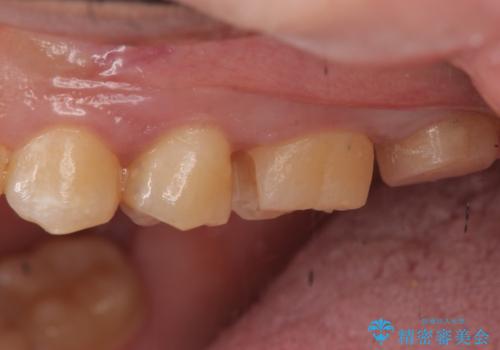

- 奥歯に穴が開いた気がするとのことで来院。

検査の結果、左上の奥歯に大きな虫歯があることが確認できました。

患者様のご希望もあり、今回はセラミックでの治療となりました。

- 左上6:セラミックインレー/77,000円 左上7:仮歯+ジルコニアクラウン/11,000+110,000円費用は治療当時の料金となります

歯の表面に穴が開くほどの虫歯は歯の中でかなり大きくなっていることが多いです。

虫歯の除去後は適合の良い修復物を入れることで今後の虫歯リスクを減らします。